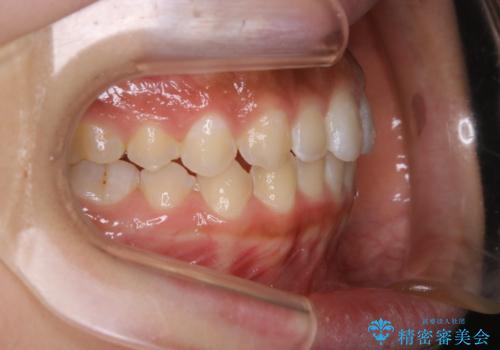

短期間ですきっ歯を改善:インビザラインLite

- 上の歯がすきっ歯なのと、歯が出ている気がするとご相談にいらした方です。

奥歯の噛み合わせに大きな問題がなく、患者様のご希望もあったため、前歯部メインで治療するインビザラインLiteで治療を行いました。

横顔のシルエットが改善し、口元もスッキリとなりました。